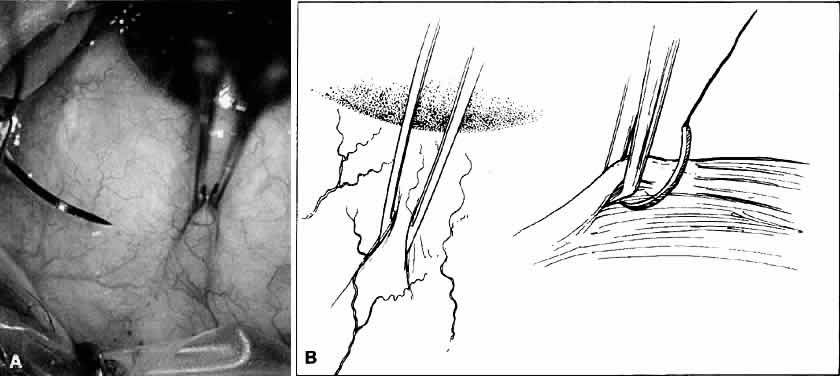

Fig. 18. A. Forceps with angled teeth can grasp tissue lying in front of the end of

the teeth. A forceps with angled teeth is seen grasping the superior

rectus muscle insertion through the conjunctiva before placement of a

bridal suture. B. The muscle is pulled off the globe by the forceps, and the suture is allowed

to pass beneath the body of the muscle. Fig. 18. A. Forceps with angled teeth can grasp tissue lying in front of the end of

the teeth. A forceps with angled teeth is seen grasping the superior

rectus muscle insertion through the conjunctiva before placement of a

bridal suture. B. The muscle is pulled off the globe by the forceps, and the suture is allowed

to pass beneath the body of the muscle.